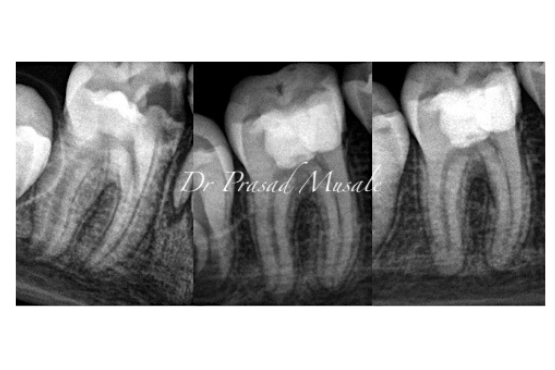

When your little one’s permanent teeth are decayed or traumatized and the root formation is incomplete, we clean them completely and place a therapeutic medicament to allow un-interrupted root formation.